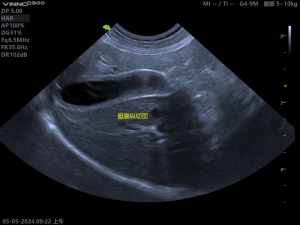

(2)胆囊粘液囊肿影像

胆囊内呈现“猕猴桃征”或“星芒状”的回声。胆囊壁增厚、胆泥淤积、可评估胆囊是否破裂。